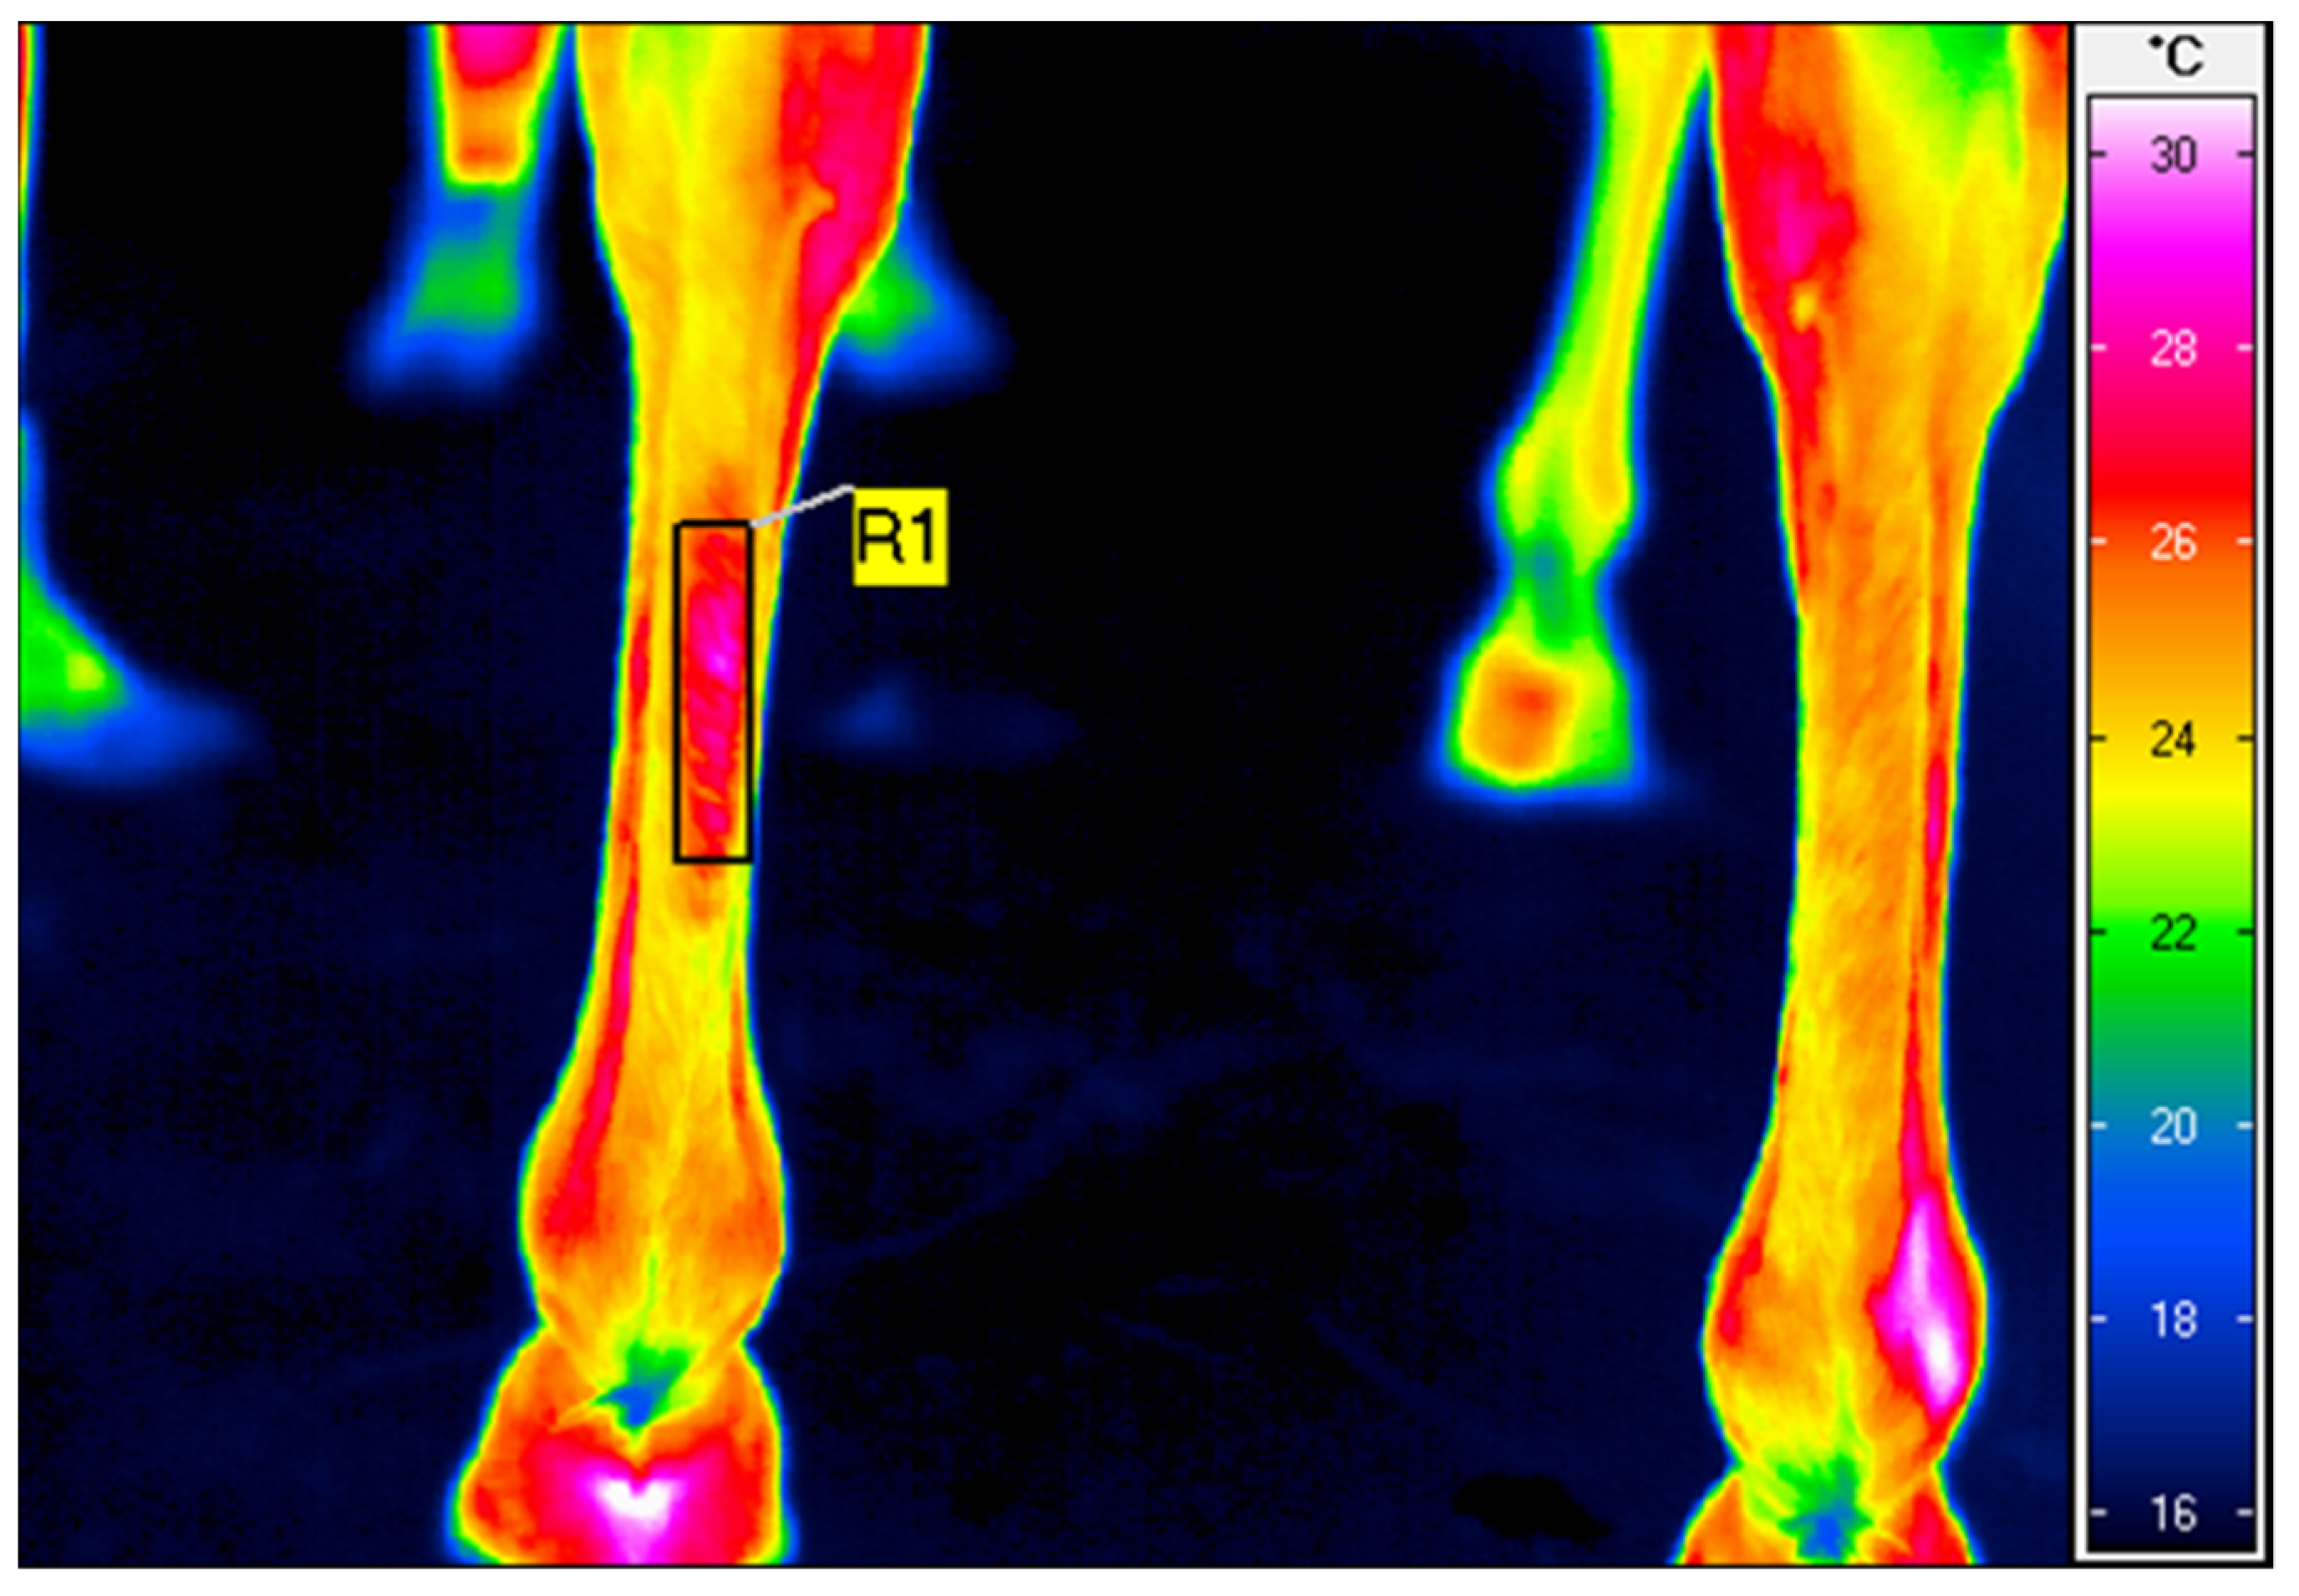

| Before HILT N = 18 | After HILT N = 18 | Change | p-Value | |

| Tavg (°C) | <0.001 | |||

| M ± SD | 21.2 ± 3.0 | 24.6 ± 2.9 | 3.5 ± 2.91 | |

| Me (Q1; Q3) | 21.3 (18.4; 23.4) | 24.4 (22.4; 26.6) | 3.4 (2.5; 4.5) | |

| Min–Max | 16.7–26.5 | 19.9–29.1 | 0.9–7.4 |